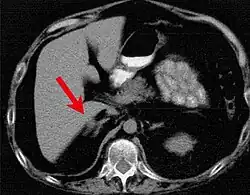

Симптомы зависят от размера, подвижности и расположения опухоли. Пятнистая пигментация кожи чаще всего встречается на лице, особенно на губах, веках, конъюнктиве и слизистой оболочке полости рта[2]. Миксома сердца может привести к тромбоэмболии, сердечной недостаточности[6] и может проявляться лихорадкой, болью в суставах, одышкой, диастолическим шумом. Миксома может развиться вне сердца, как правило, на коже и в груди. Клинически эндокринные опухоли могут проявляться в виде расстройств, характерных для синдрома Кушинга.